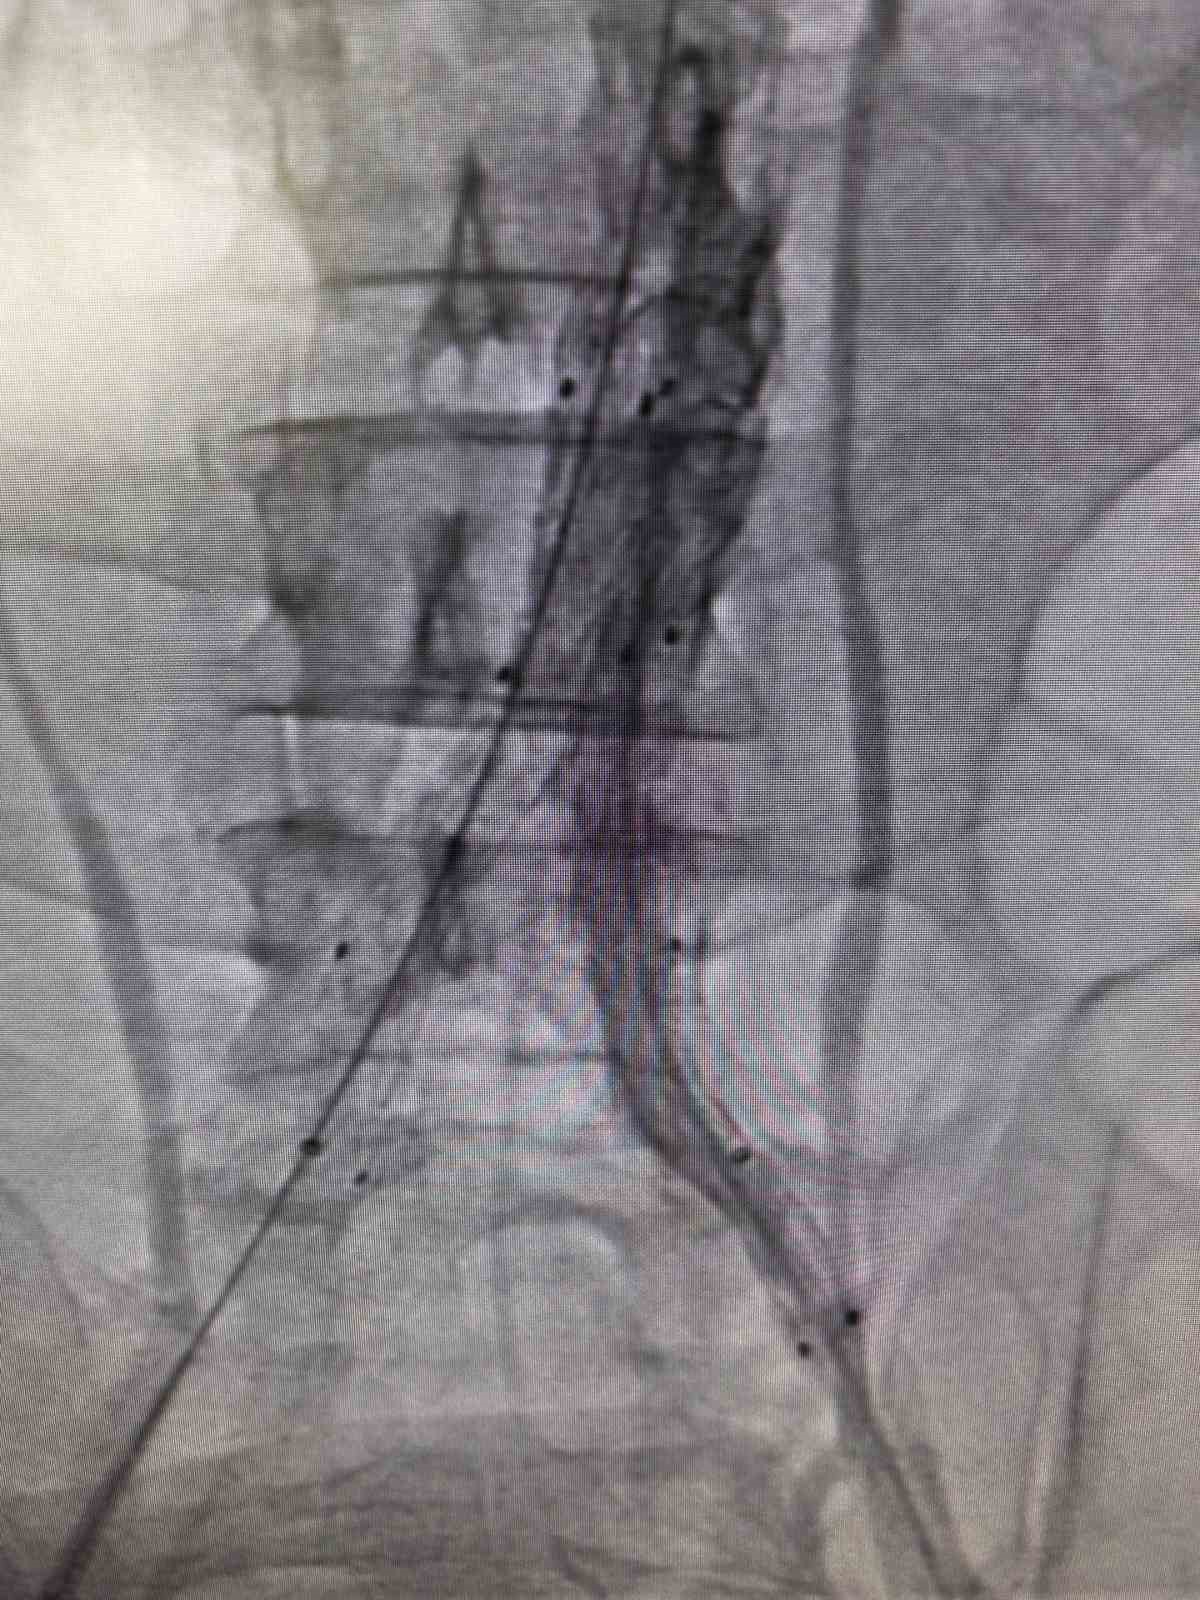

Bilecik Eğitim ve Araştırma Hastanesi’nde daha önce farklı sağlık kuruluşlarına başvuran ancak net bir tanı konulamayan hasta, acil servisinde yapılan detaylı tetkikler sayesinde doğru tanıya ulaştırıldı. Şiddetli sırt ve karın ağrısı şikâyetiyle hastaneye başvuran 39 yaşındaki Mehmet D.’nin acil serviste çekilen ileri görüntüleme tetkiklerinde, kalpten çıkan ana damarın iç duvarında yırtılma olduğu belirlendi. Hayati risk taşıyan bu durum üzerine hasta, kalp ve damar cerrahisi ekibi tarafından acil olarak değerlendirmeye alındı.Hasta, Kalp ve Damar Cerrahisi Uzmanı Op. Dr. Elmas Üreyen tarafından kapalı yöntemle tedavi edildi. Damar içinden girilerek yapılan işlem sırasında, yırtılan ana damarın içine özel bir stent yerleştirildi ve damar içten onarıldı. Açık ameliyata gerek kalmadan gerçekleştirilen bu yöntem sayesinde hasta kısa sürede rahatladı.Tedavi sonrası yakından takip edilen hastanın ağrılarının tamamen geçtiği, genel sağlık durumunun iyi olduğu gözlemlendi. Kontrollerinin sorunsuz seyretmesi üzerine hasta sağlıklı bir şekilde taburcu edildi.